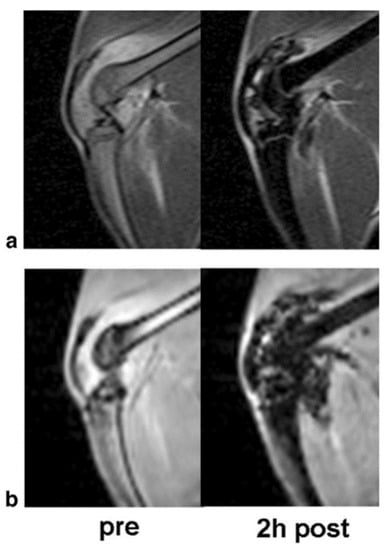

2.2. IONPs as MRI Contrast Agents

2.3. Contrast Agent Application in MRI

- Simon, G.H.; von Vopelius-Feldt, J.; Wendland, M.F.; Fu, Y.; Piontek, G.; Schlegel, J.; Chen, M.H.; Daldrup-Link, H.E. MRI of arthritis: Comparison of ultrasmall superparamagnetic iron oxide vs. Gd-DTPA. J. Magn. Reson. Imaging 2006, 23, 720–727. [Google Scholar] [CrossRef] [PubMed]